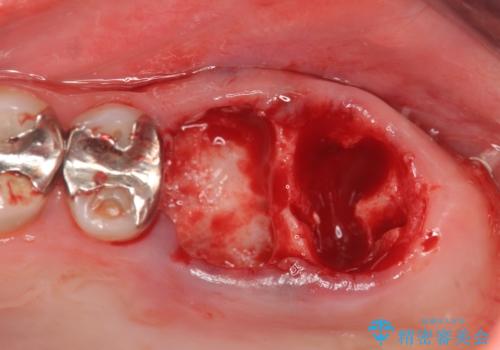

X線検査の結果、左上6には歯根破折、左上7には銀歯の下に大きな虫歯の再発が認められ共に抜歯をせずには症状の改善が見込めない状況です。

奥歯を2本失ったのち、しっかりと噛める環境へと整備するため、しっかりと骨の造成を行い清掃性を高めたインプラント治療を行っていくこととしました。

インプラントの仕上がりを見越して、ただ埋入するだけではなく長期的な予後を見込むには清掃のしやすい環境を整備することが大切です。

今回は大きく吸収してしまった歯槽骨をしっかりと造成することで、歯間ブラシを行いやすいインプラント周囲環境を整備することができました。